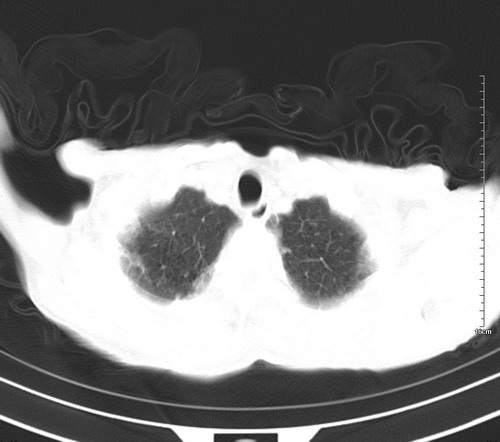

后中纵隔团块影,伴气管、食道受压移位,首先考虑转移瘤,肝s5段低密度灶。建议增强检查,另外其结肠是否有问题请提供,右肺部分肺叶局限含气增多,考虑局限肺气肿。

病人,女,79岁,主要因腹疼二月入院,彩超,肝,胆,脾,未见异常,胸透上消化道造影未见异常,化验白细胞增高,内科医生让做胸部ct检查,因为熟人多做了腹部(外科会诊考虑胆囊炎).现ct片如下请假各位战友.